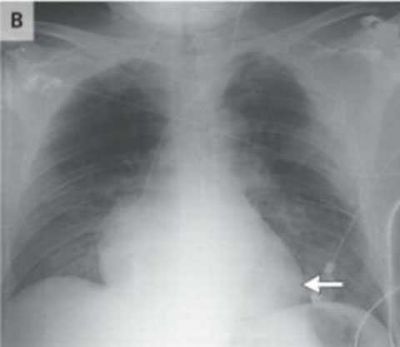

Сделав пациенту рентген и компьютерную томографию медики выяснили, что его сердце перевернулось на 90 градусов и переместилось в правую часть груди. Они также отметили, его аорта и легочная артерия была повернута вправо.

Мужчина также получил многочисленные переломы ребер, коллапс легкого, синяки на обоих легких и разрыв селезенки. Тем не менее, несмотря на все полученные травмы, он оставался в сознании. Единственным признаком проблем с сердцем было небольшое падение кровяного давления и небольшое увеличение частоты его сердечных сокращений.